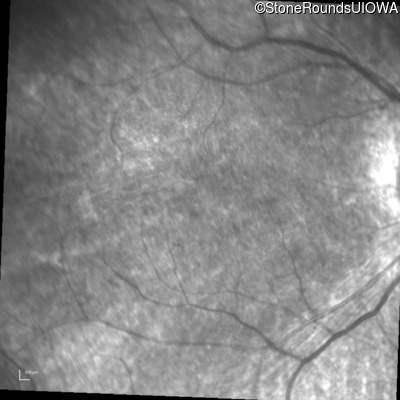

Infrared Fundus Photograph - Right - 20/80 -1

Exemplar